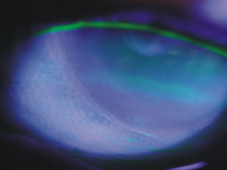

圖二、乾眼症引發的結膜?胞受損以

(Rose Bengal染色)